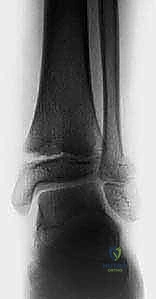

- الأشعة السينية (X-rays): هي الخطوة الأولى والأساسية. يتم التقاط صور من زوايا متعددة (أمامية، جانبية، ومائلة) لتقييم الكسر.

- كسور سالتر-هاريس النوع الثالث (Type III): كسر يمر عبر لوح النمو ثم يتجه للأسفل ليخترق المشاشة والسطح المفصلي. هذا الكسر داخل المفصل يتطلب دائمًا تقييمًا جراحيًا لضمان عدم وجود أي تفاوت في سطح المفصل.

- كسور سالتر-هاريس النوع الرابع (Type IV): كسر عمودي يمر عبر الكردوس، ثم لوح النمو، ثم المشاشة وصولاً إلى المفصل. هذا النوع يحمل خطورة عالية جدًا لإغلاق لوح النمو وتكوين جسر عظمي (Bony Bar) إذا لم يتم تثبيته جراحياً بدقة تشريحية مطلقة.